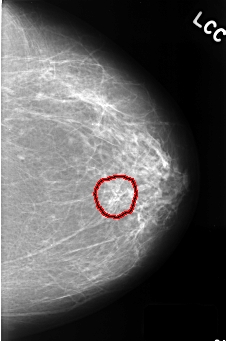

FILE: C_0390_1.LEFT_CC.OVERLAY

TOTAL_ABNORMALITIES 1

ABNORMALITY 1

LESION_TYPE CALCIFICATION TYPE PLEOMORPHIC DISTRIBUTION CLUSTERED

ASSESSMENT 4

SUBTLETY 4

PATHOLOGY BENIGN

TOTAL_OUTLINES 1

BOUNDARY